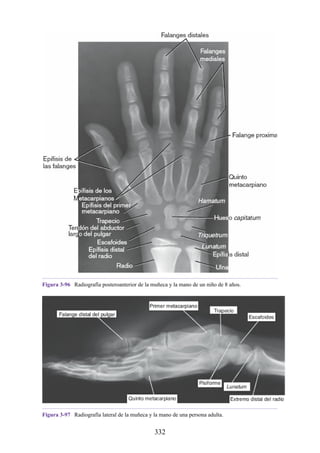

Notas clínicas

Lesiones ligamentosas